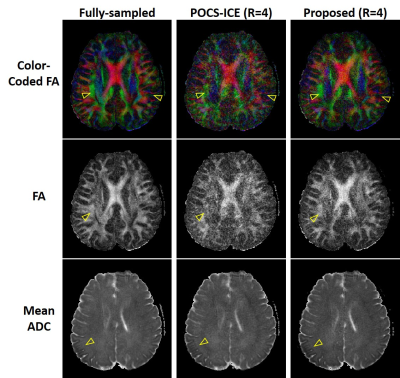

Figure 4. DTI metrics calculated from the diffusion-weighted images reconstructed by the fully-sampled data, the highly undersampled data of R=4 with POCS-ICE method and the our proposed joint reconstruction. The FA and color-coded FA maps from our proposed reconstruction are closer to those from the fully-sampled reference, and the mean ADC has reduced aliasing artifacts compared with POCS-ICE. Note that raw data were acquired using an 8-channel head coil.